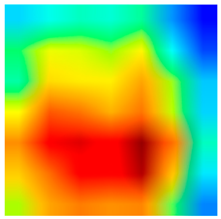

2.4. Model Interpretability

3.6. Visualizing Interpretability in CRC Classification Using ADFMs

| Tissue Class | Original Image | Heatmaps | Superimposed Image |

|  |  |  |

|  |  |  |

|  |  |  |

|  |  |  |